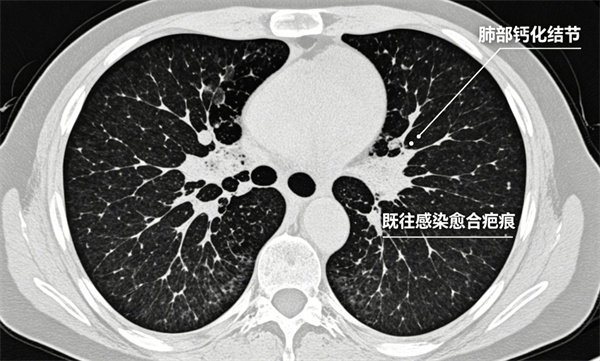

3钙化结节

多为既往感染愈合后留下的疤痕,类似皮肤痘印。

几乎都是良性,一般无需治疗、无需复查。

4条索影 斑片影

肺部炎症吸收后留下的纤维痕迹,属于良性陈旧性改变。

无不适症状者,通常不影响健康。